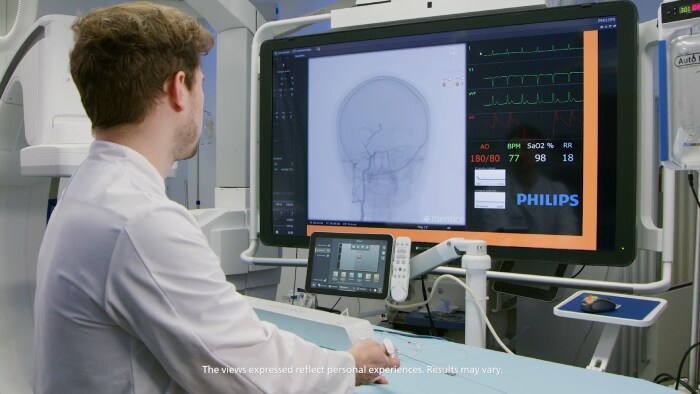

Direct to Angio Suite

Time to reperfusion is fundamental in reducing morbidity and mortality in acute stroke cases1, 2, 3. In patients presenting directly to an endovascular-capable center, emphasis has now been placed on fast door-to-imaging times and fast imaging to groin access times. Watch the video to see how this works.

Experts explain how Direct to Angio Suite workflows shorten door to re-perfusion times for their ischemic stroke patients and how more patients can benefit from mechanical thrombectomy through changed guidelines.